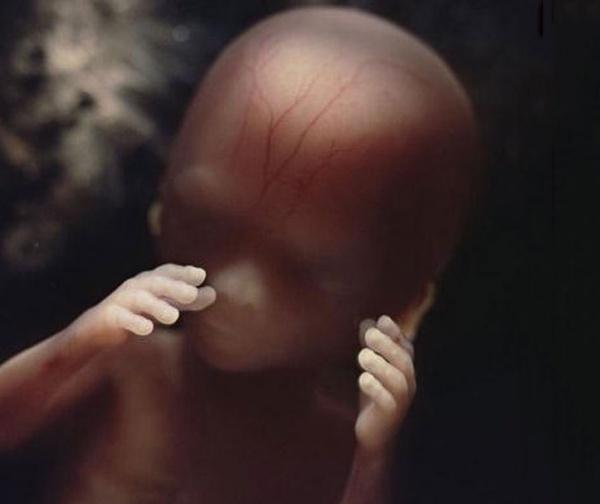

Οι αρτηρίες του αίματος φαίνονται μέσα από το δέρμα

18 εβδομάδων. Το έμβρυο τώρα μπορεί να ακούει ήχους από τον έξω κόσμο